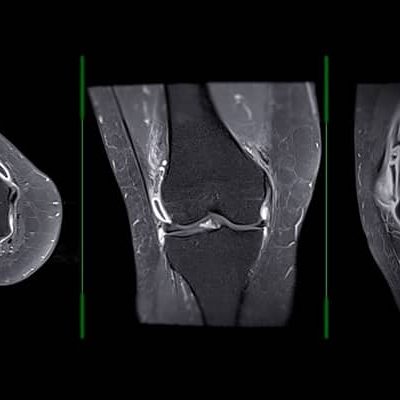

It has been cited to be as accurate as MRI imaging but at Banbury Private Physiotherapy Practice we have links to MRI scanning at the Cobalt Unit in Cheltenham with Radiological reports necessary for secondary care/specialist review.